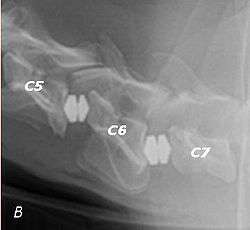

X-ray of wobbler disease in a dog

Wobbler disease is probably inherited in the Borzoi, Great Dane, Doberman, and Basset Hound.[2] Instability of the vertebrae of the neck (usually the caudal neck) causes spinal cord compression. In younger dogs such as Great Danes less than two years of age, wobbler disease is caused by stenosis (narrowing) of the vertebral canal[3] related to degeneration of the dorsal articular facets and subsequent thickening of the associated joint capsules and ligaments.[1] A high-protein diet may contribute to its development.[4] In middle-aged and older dogs such as Dobermans, intervertebral disc disease leads to bulging of the disc or herniation of the disc contents, and the spinal cord is compressed.[3] In Great Danes, the C4 to C6 vertebrae are most commonly affected; in Dobermans, the C5 to C7 vertebrae are affected.[5]